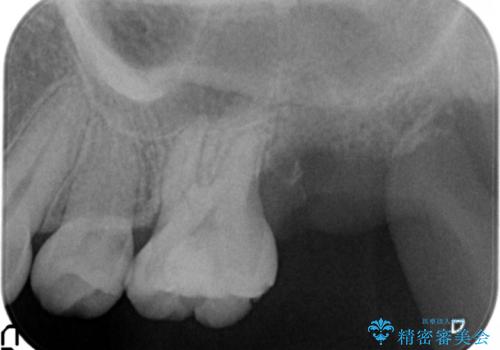

精査したところ、左上の奥歯の間(左上56間)にう蝕を認めました。

う蝕を丁寧に除去したのち、セラミックインレーによる修復を行いました。